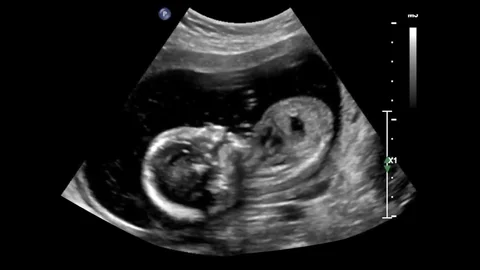

Obstetric USG

It is a safe, non-invasive imaging test that uses sound waves to create real-time images of a developing fetus in the uterus. It is used to confirm pregnancy, monitor fetal growth and development, determine gestational age, check for multiple pregnancies, and screen for abnormalities or birth defects.